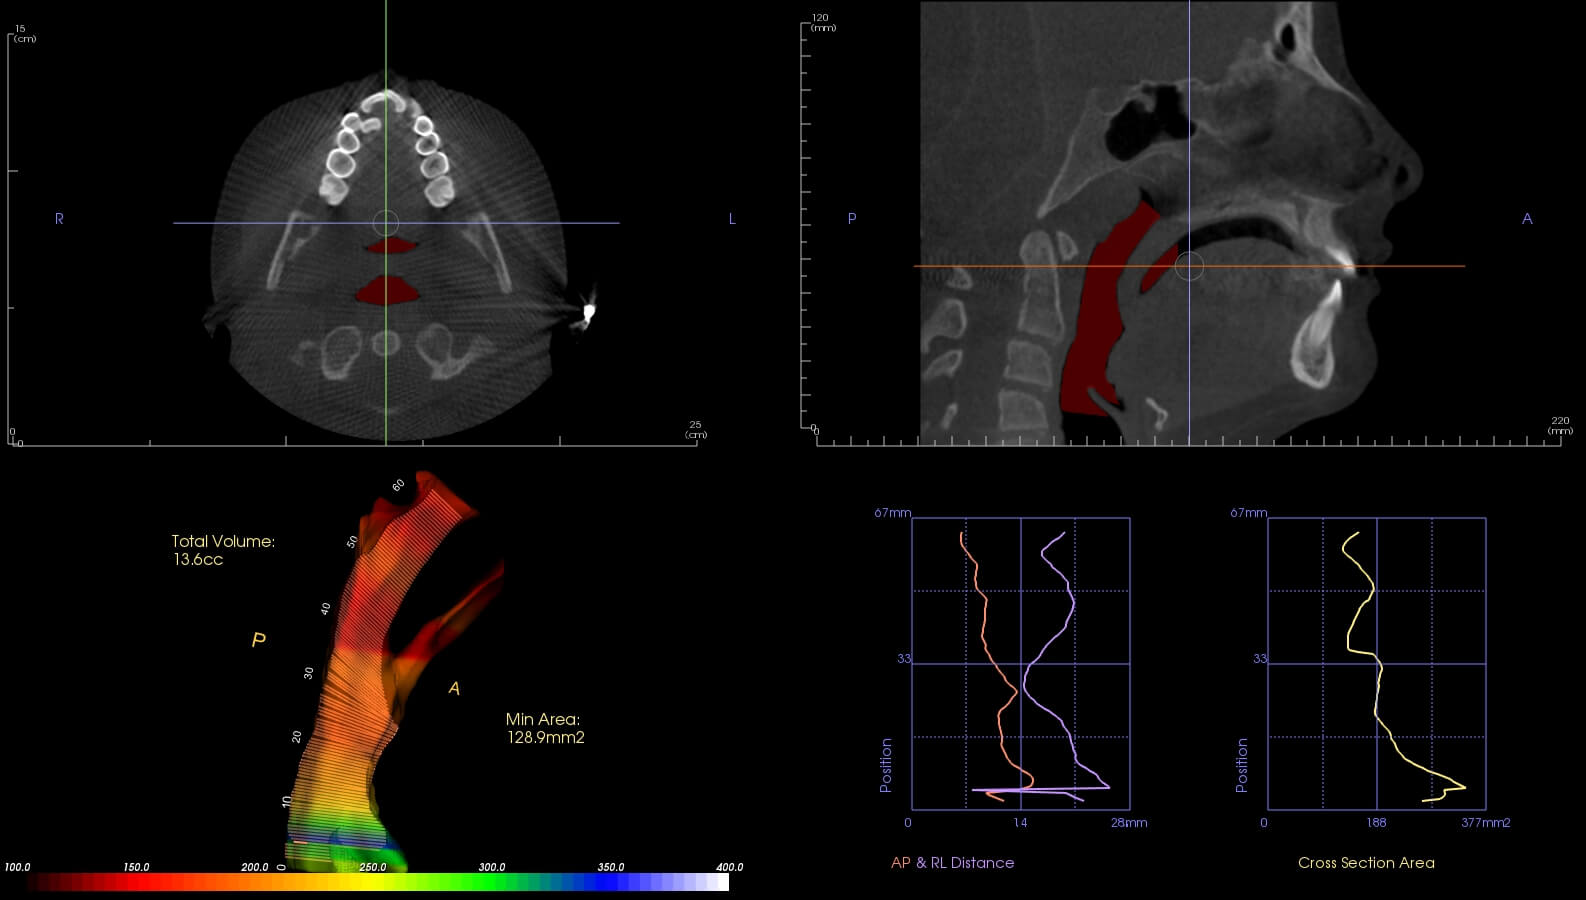

This is a before and after of a tongue tie and release procedure. This patient struggled performing certain speech sounds and reported a more comfortable tongue position and easier speech after the procedure.